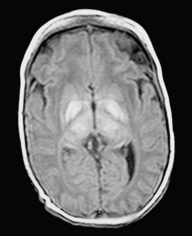

Thalamus- und Basalgangliennekrose (Abb. 4.11).

Durch die Verlaufsbeurteilung der klinischen Symptome, der bildgebenden Diagnostik und des aEEG und des EEG lassen sich in vielen Fällen schon früh Aussagen zur Prognose der Kinder machen. Faktoren, die mit einer schlechten Prognose assoziiert sind, sind in der Übersicht aufgeführt. Im Ultraschallbild zeigt sich oft eine „verwaschene“ Parenchymzeichnung als Ausdruck einer diffusen neuronalen Nekrose oder eines Hirnödems. Als Zeichen einer Thalamusnekrose können in den ersten Lebenswochen ausgeprägte Echoverdichtungen in dieser Region darstellbar sein. Eine Magnetresonanztomographie (MRT) kann bereits in den ersten Lebenstagen deutliche Signalveränderungen aufweisen (Abb. 4.11). Eine nützliche, jedoch nicht immer durchführbare Untersuchung ist die Magnetresonanzspektroskopie (MRS). Ein Nachweis von hohen Laktatsignalen im Gehirn sowie niedrigen Signalen für N-Acetyl-Aspartat, einem Marker für Neuronen, spricht für eine schwere Hirnschädigung mit schlechter Prognose.